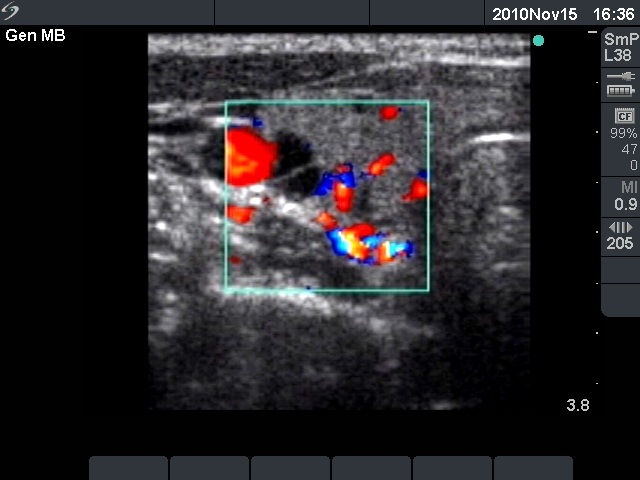

Initial examination (first row of images):

Ultrasonography: The right thyroid was echonormal and contained several small, insignificant lesions. There was a hypoechogenic lesion with blurred borders in the central and in the ventro-medial part of the left thyroid with increased intranodular blood flow.